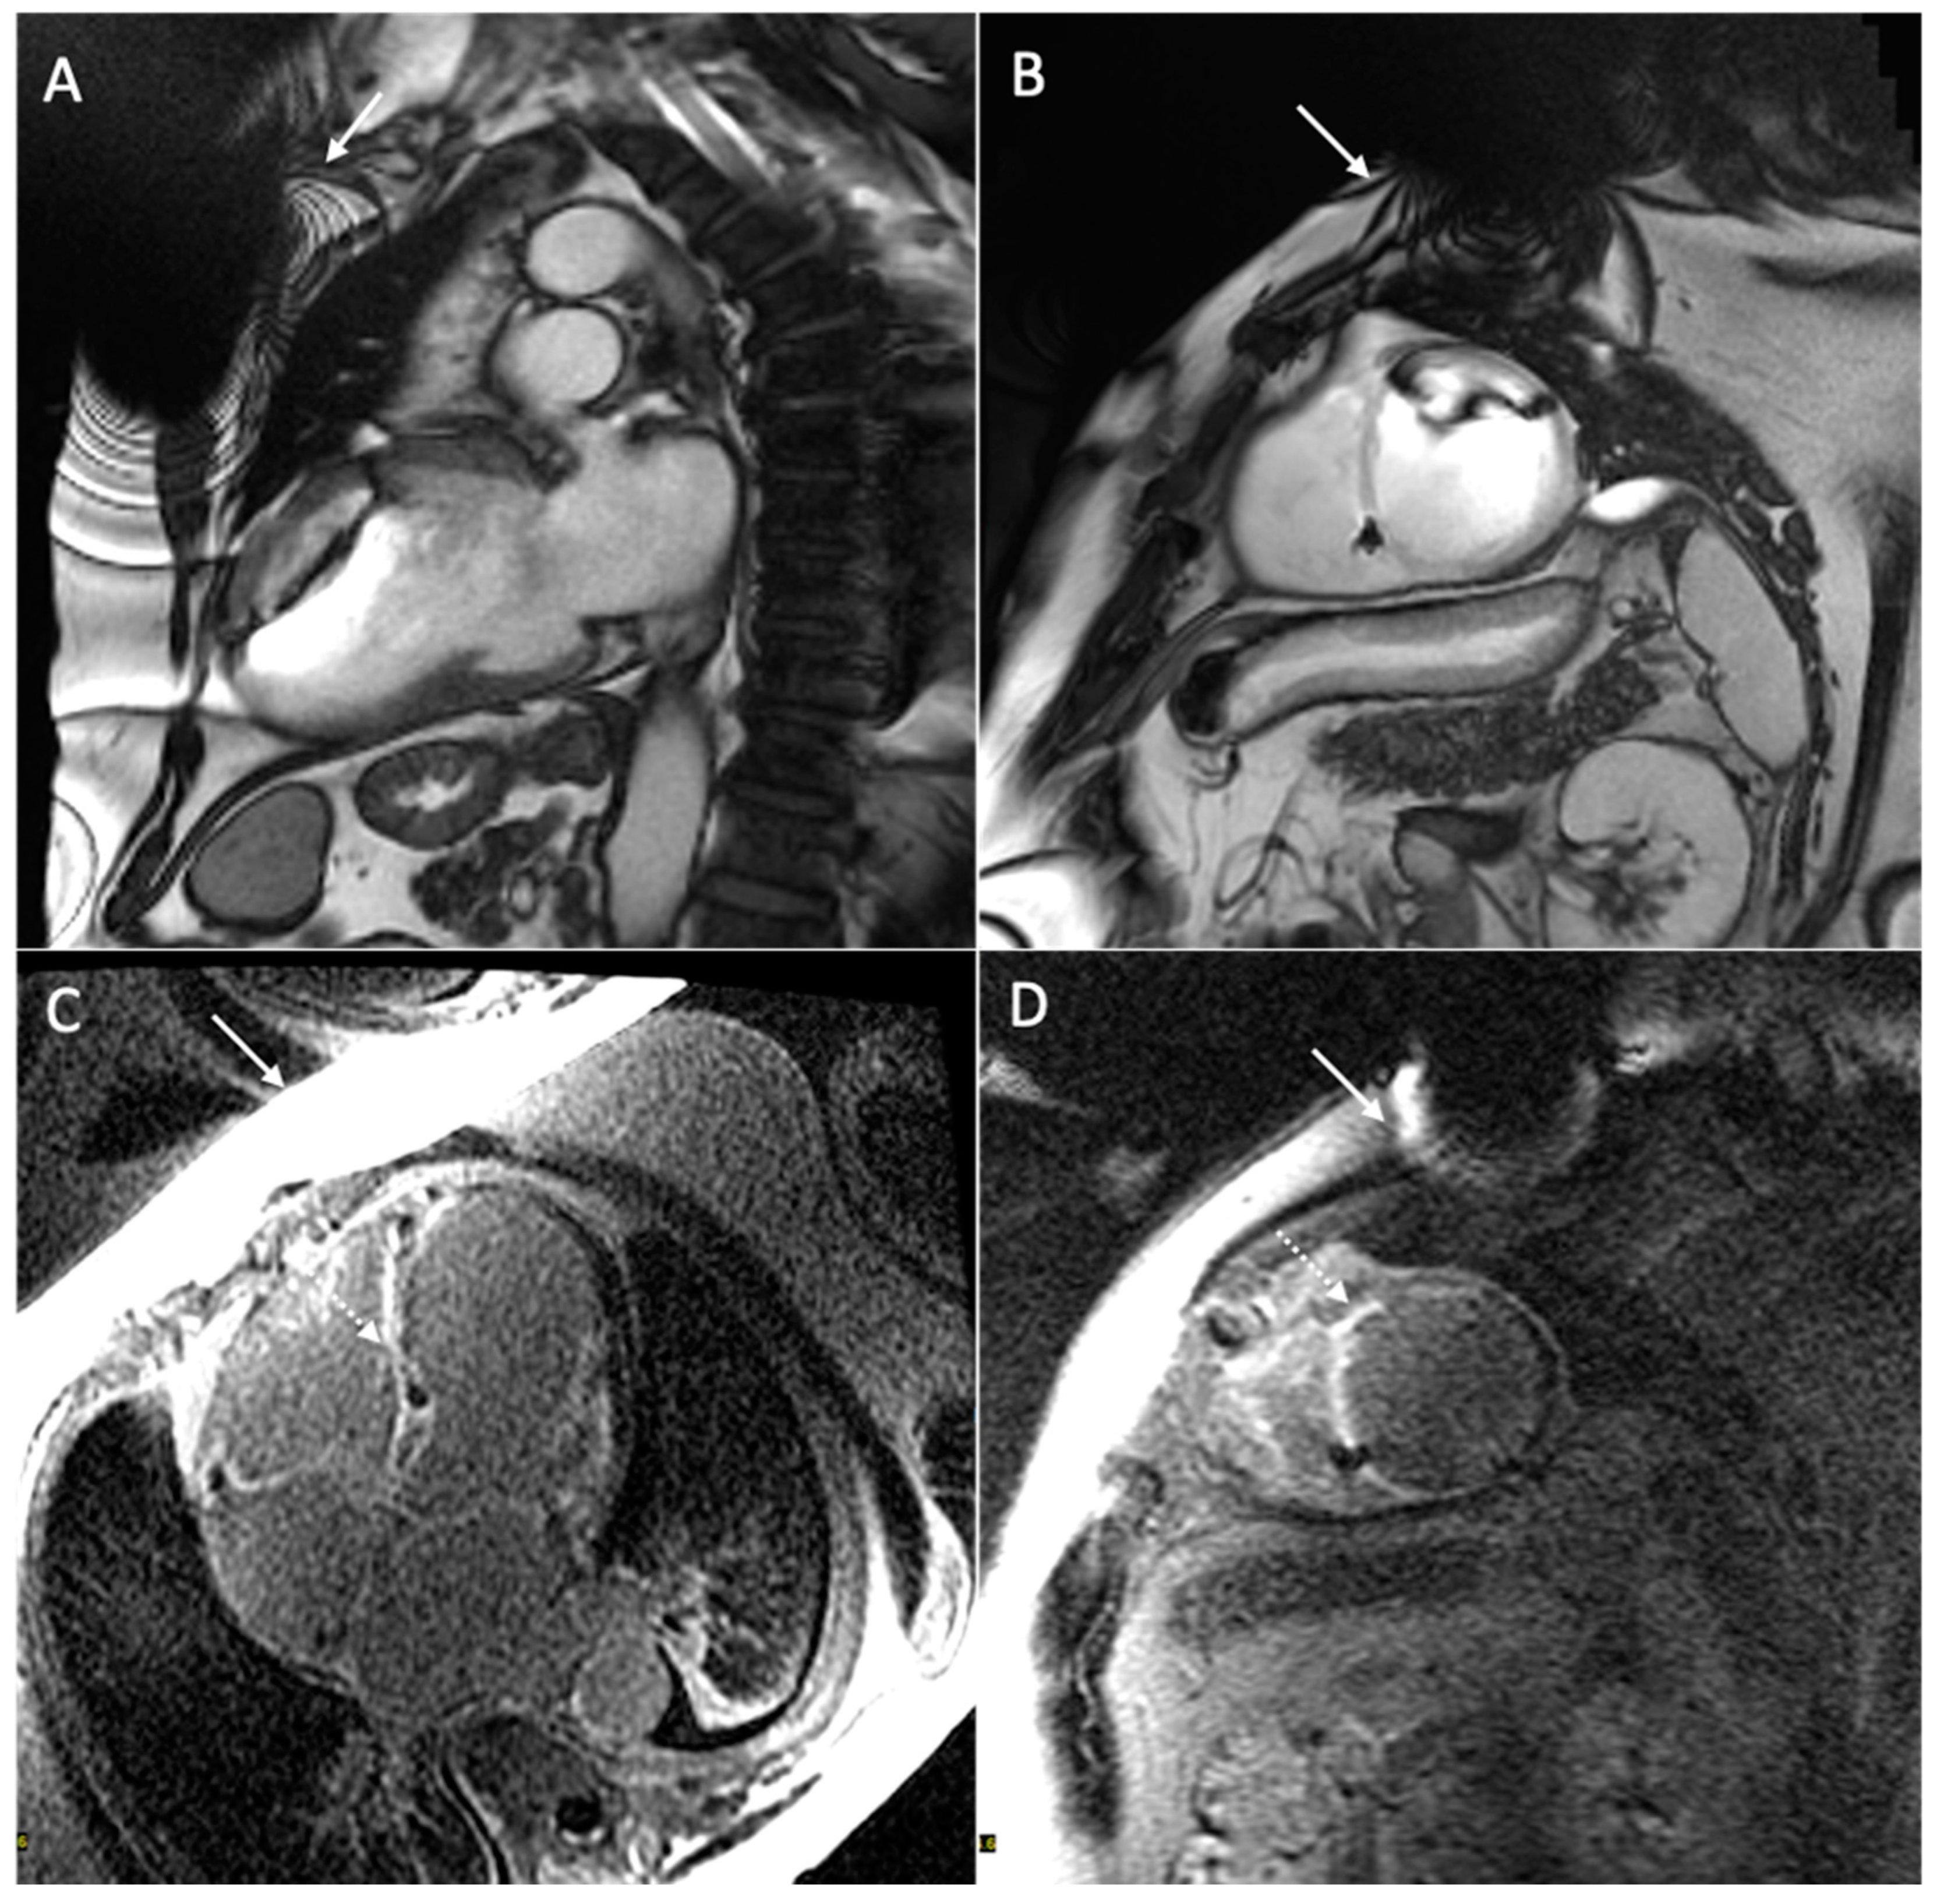

6. Issue: Artifact

- Vuorinen, A.-M.; Lehmonen, L.; Karvonen, J.; Holmström, M.; Kivistö, S.; Kaasalainen, T. Reducing cardiac implantable electronic device–induced artefacts in cardiac magnetic resonance imaging. Eur. Radiol. 2022, 33, 1229–1242. [Google Scholar] [CrossRef] [PubMed]

- Runge, M.; Ibrahim, E.-S.H.; Bogun, F.; Attili, A.; Mahani, M.G.; Pang, Y.; Horwood, L.; Chenevert, T.L.; Stojanovska, J. Metal Artifact Reduction in Cardiovascular MRI for Accurate Myocardial Scar Assessment in Patients with Cardiac Implantable Electronic Devices. Am. J. Roentgenol. 2019, 213, 555–561. [Google Scholar] [CrossRef]

- Ibrahim, E.-S.H.; Runge, M.; Stojanovska, J.; Agarwal, P.; Ghadimi-Mahani, M.; Attili, A.; Chenevert, T.; Harder, C.D.; Bogun, F. Optimized cardiac magnetic resonance imaging inversion recovery sequence for metal artifact reduction and accurate myocardial scar assessment in patients with cardiac implantable electronic devices. World J. Radiol. 2018, 10, 100–107. [Google Scholar] [CrossRef]

| Types of Artifacts | Factors that Influence Artifacts | High Artifact | Low Artifact |

|---|---|---|---|

| Signal loss artifact Hyperintensity artifact | CIED’s dimension | Large device | Small device |

| CIED’s position | Left-sided implantation | Right-sided implantation | |

| Magnetic susceptibility | High ferromagnetic component | Low ferromagnetic components | |

| High static MF | Low static MF | ||

| Distance from the region of interest | Proximity to the heart | Elevate the patient’s arm | |

| MRI sequences used | Cine SSFP | SGE sequences | |

| LGE sequence with a bandwidth of about 1 kHz | LGE sequence with a wide bandwidth |